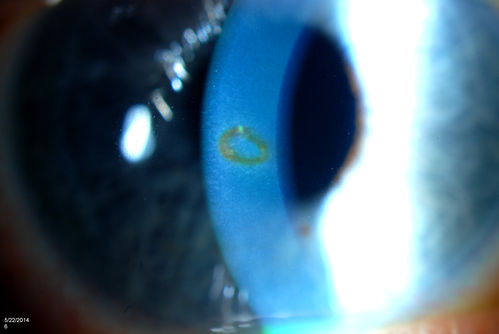

Foreign Body "Rust Ring"

Patient complained of redness and tearing with white discharge. Patient was working with a grinding wheel on a vehicle. Slit lamp exam shows a rust ring barley off center. FBS was removed with Algiers Brush.

Corneal Rust Ring